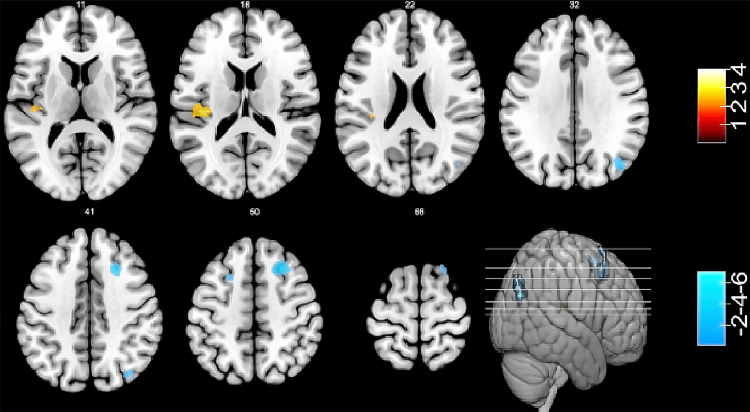

Results: DOP patients exhibited significantly decreased BMD, T-scores, MoCA scores, and osteocalcin (OC) levels compared to controls (p<0.05). FC analysis revealed: 1) Reduced connectivity between the left middle temporal gyrus (increased ReHo) and middle occipital gyrus; 2) Enhanced connectivity between the right angular gyrus (increased ReHo) and left Rolandic operculum; 3) Weakened the left precuneus (increased ReHo) and right superior/left middle frontal gyri. These alterations correlated with deficits in visual processing, working memory, and executive function.

Conclusion: Distinct FC reorganization in DOP patients reflects synergistic effects of metabolic and skeletal pathologies on neural networks, potentially mediating cognitive decline through visual pathway disruption and prefrontal-default mode network decoupling. The findings highlight neuroimaging biomarkers for metabolic bone disease-related cognitive disorders.